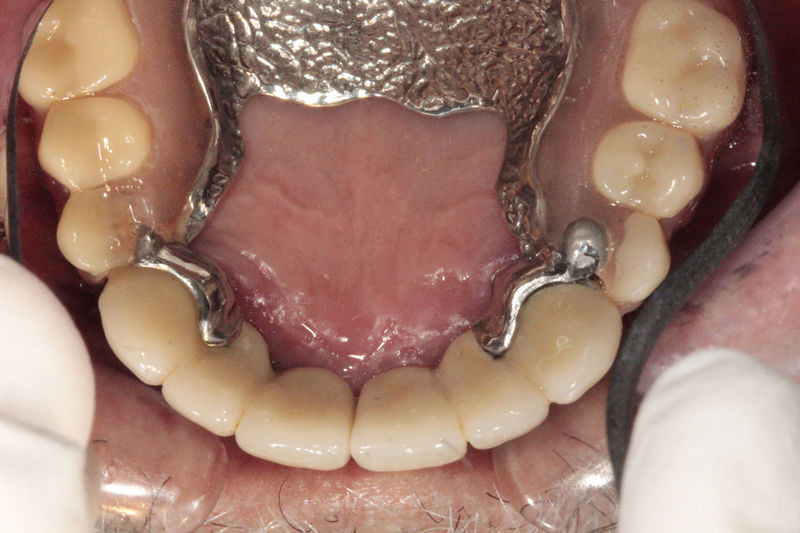

Restauraciones fabricadas en el laboratorio los cuales se usan para reemplazar dientes ausentes usando dientes, coronas y/o tejidos blandos como soporte y que pueden y deben de ser removidas para su limpieza. Para poder enviar el caso al laboratorio se toman impresiones utilizando materiales de impresión o técnicas modernas digitales.